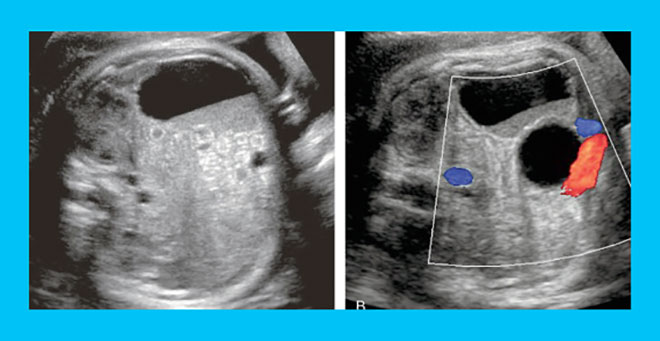

- УЗИ. В полости кисты отсутствуют кровеносные сосуды. Это является отличительной характеристикой лютеинового новообразования.

Когда киста регрессирует в период между циклами, шансы на зачатие повышаются. При этом гормональный фон не должен быть нарушен. Во время УЗИ доктор визуализирует 2 желтых тела. Одно из них будет находиться в фазе регрессии и иметь малые размеры.